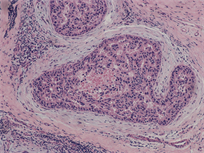

Samples were retrieved from 104 ductal breast cancer patients, tissues were made into paraffin blocks and HE staining, diagnosed by pathological doctors. Pathological type: 9 cases of carcinoma in situ (Figure 1(a)), 95 cases of invasive ductal carcinoma (Figure 1(b)).

Figure 1. (a) Pathological type: 9 cases of carcinoma in situ; (b) 95 cases of invasive ductal carcinoma.